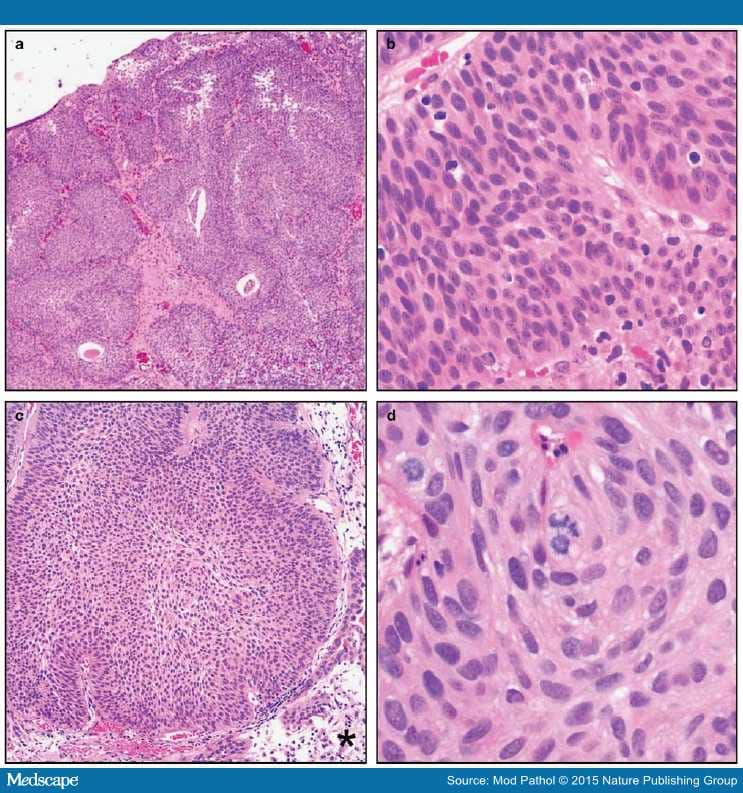

Photomicrography of bladder tumors. A -Plasmacytoid urothelial …